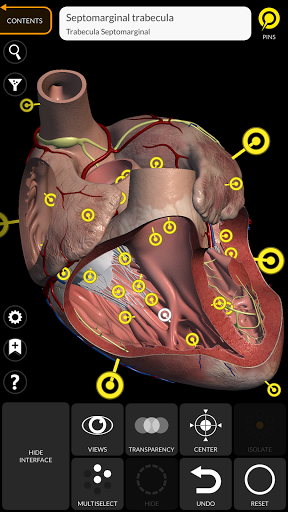

"Anatomy 3D Atlas" дозволяє легко та інтерактивно вивчати анатомію людини.

Завдяки простому та інтуїтивно зрозумілому інтерфейсу можна спостерігати кожну анатомічну структуру під будь-яким кутом.

Анатомічні 3D-моделі особливо деталізовані та мають текстури з роздільною здатністю до 4k.

• Серцево-судинна система

• Функція закладок для збереження користувальницьких переглядів

• Вибравши модель або шпильку, з’явиться відповідний анатомічний термін